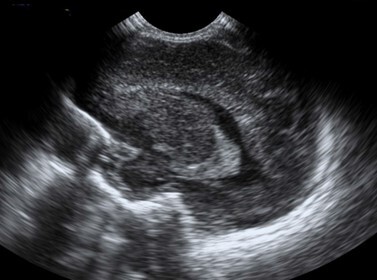

Neonatology Choroid Plexus 3 Image